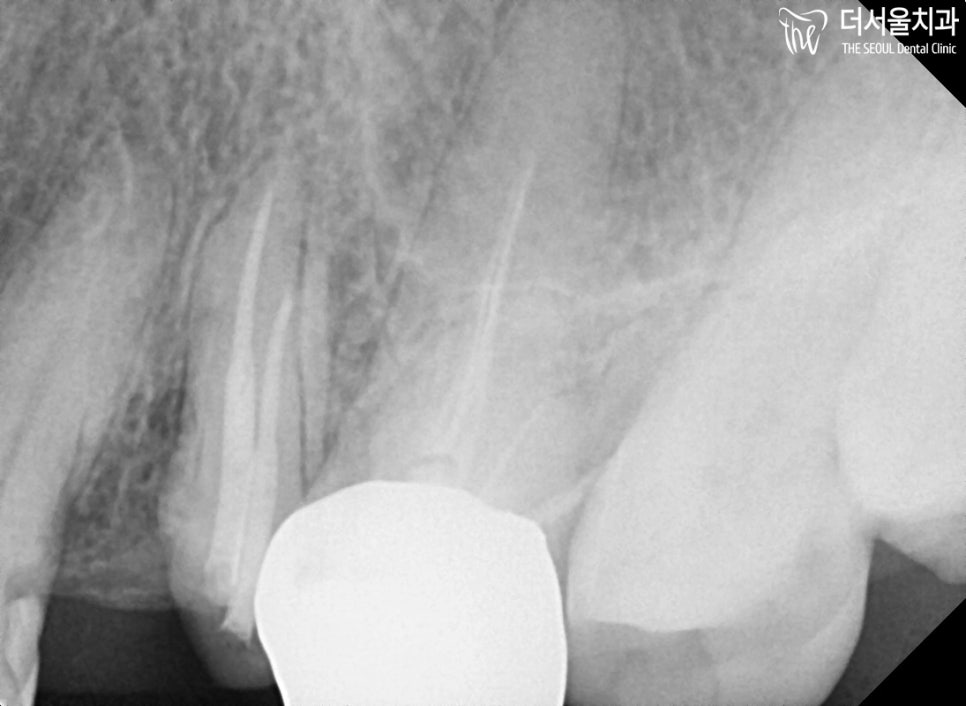

1. 초진

윗 어금니 깨짐 문제로 찾아오셨는데요.

거의 뿌리만 남아있는 채로

살리기 힘들겠다는 생각이 들었습니다.

좀 더 정확한 진단을 하기 위해서

치근단 엑스레이를 촬영해봤습니다.

이미 신경치료를 받았던 이력이 있었으며,

치아를 살리기에는 너무 많이 깨져

진행하기 힘든 상태였습니다.